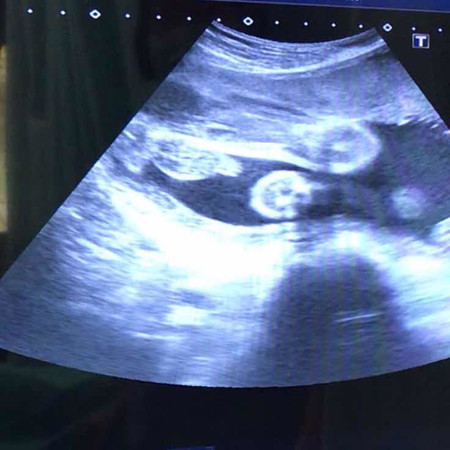

อันนี้คือชัดแล้วใช่ไหมคะ ว่าเป็น ผู้ชาย?

ขอดูรูปอัลตราซาวด์ เพศชายของแต่ละบ้านหน่อยคะ? 27w